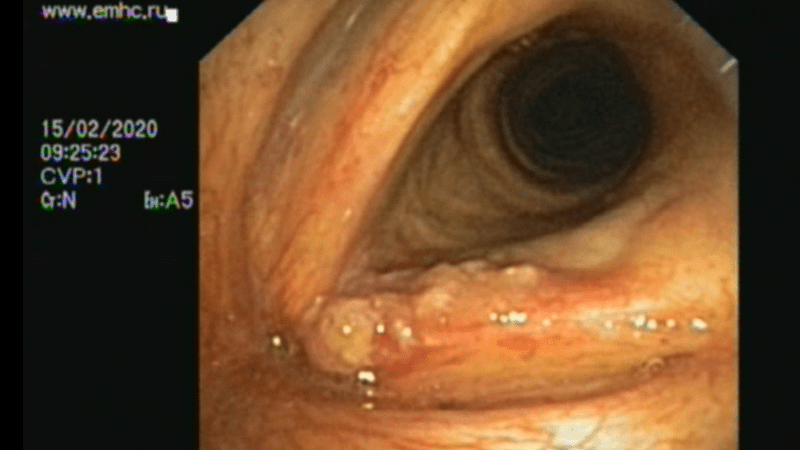

3. Непрямая ларингоскопия.

4. Видеоларингоскопия с флуоресцентной диагностикой, ускоспектральный режим и т.д.